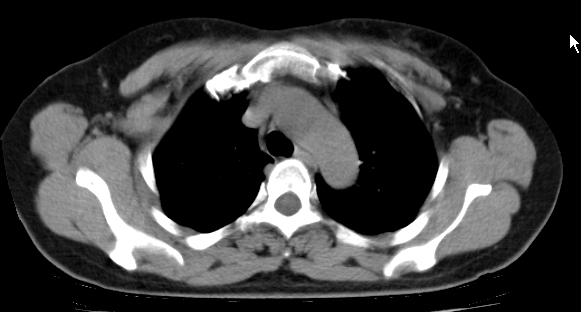

标题: CT25227:背部疼痛伴双侧胸壁痛2月,食欲差。 [打印本页]

标题: CT25227:背部疼痛伴双侧胸壁痛2月,食欲差。

肺结核并胸椎结核?请各位高手指教。

用椎体的条件来扫胸椎呀!考虑1左侧胸膜小结节形成2椎体结核并冷脓肿形成

左肺结核灶,胸椎结核并冷脓肿。

左肺结核灶,胸椎结核并冷脓肿